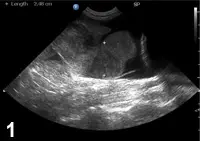

Obstructive shock is caused by any obstruction or maldistribution of blood flow that results in a decreased preload and subsequent decreased cardiac output. Causes of obstructive shock include gastric dilatation–volvulus (GDV), caval syndrome from heartworm disease, and pericardial effusion (Figure 3). Therapy involves identification and correction of the underlying cause of the obstruction—for example, stomach decompression in GDV or pericardiocentesis for pericardial effusion. Similar to hypovolemic shock treatment, IV fluid therapy can be beneficial for cases of obstructive shock.

A radiograph shows a canine thoracic cavity with clear visibility of the heart, lungs, and spine. The image highlights the diaphragm and surrounding structures, providing insight into the animal's respiratory and cardiovascular health.

Figure 3 Ventrodorsal thoracic radiograph with severe, globoid cardiomegaly